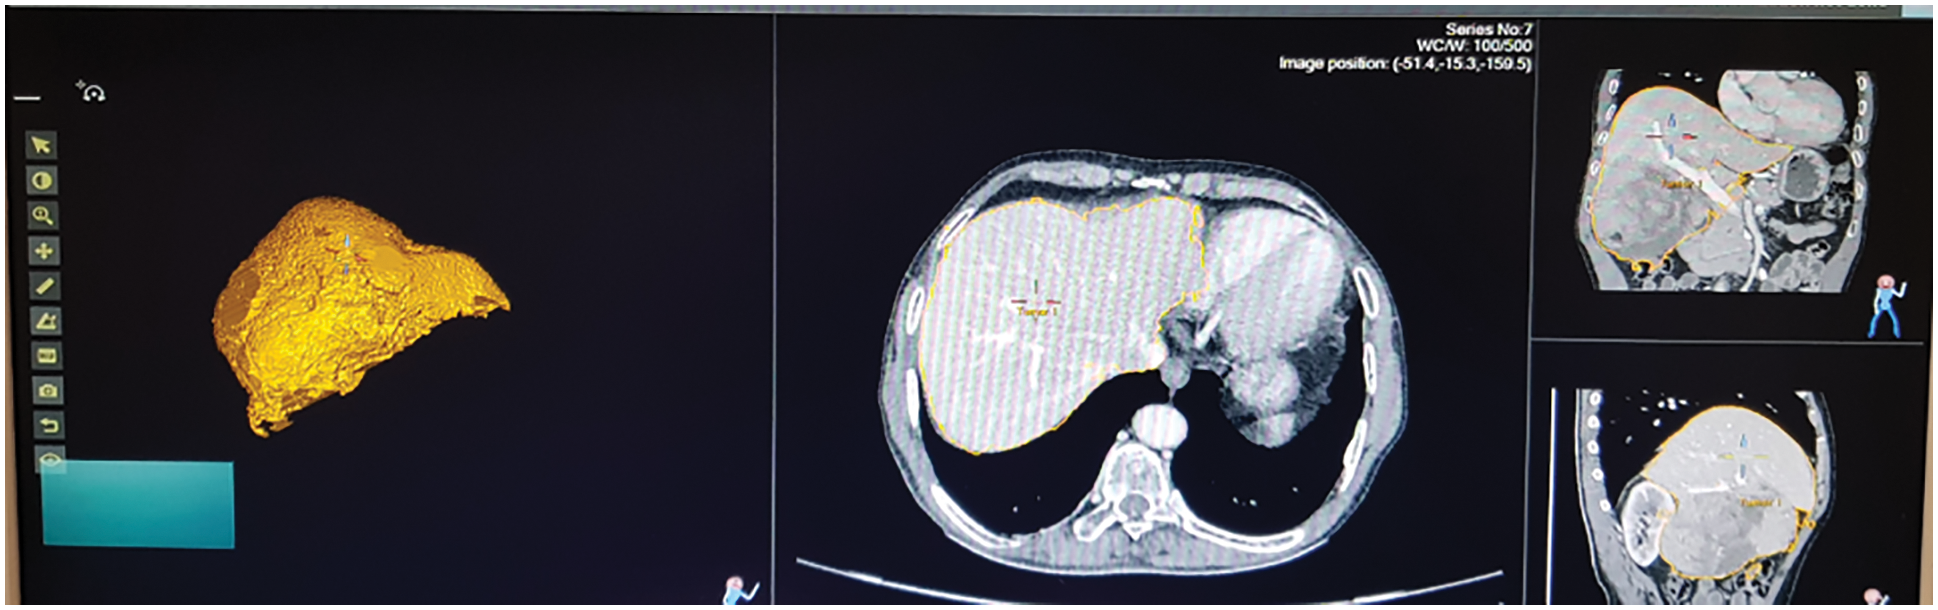

Fig. 13 shows the ultrasound value of medium fatty liver patient. The total liver volume is 1467 cc, right liver volume is 445.9 cc and left liver volume is 1021.88 cc. The medium fatty liver signal obtained from male patient age 70. Fig. 14 shows the ultrasound of mild fatty liver patient. The total liver volume is 961.86 cc, right liver volume is 365.93 cc and left liver volume is 595.33 cc. The mild fatty liver male patient at age 70. The signals from fatty liver are obtained from fatty liver sensor for sever mild and moderate fatty liver patients. The statistical parameters of the fatty liver signal from TQWT and the ultrasound lab values are correlated using gaussian regression modelling.

Figure 14: Ultrasound of mild fatty liver patient